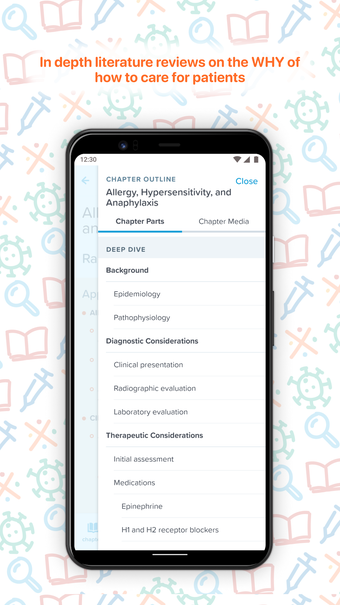

EM:RAP brengt alle beste en meest relevante informatie samen op één plek om het gemakkelijk te maken om klinische vragen te beantwoorden in een noodsituatie of een urgente situatie. Het is een echt uitgebreide, peer-reviewed, klinische bron voor spoedeisende en urgente zorggeneeskunde die u overal, altijd en op elk apparaat kunt gebruiken.